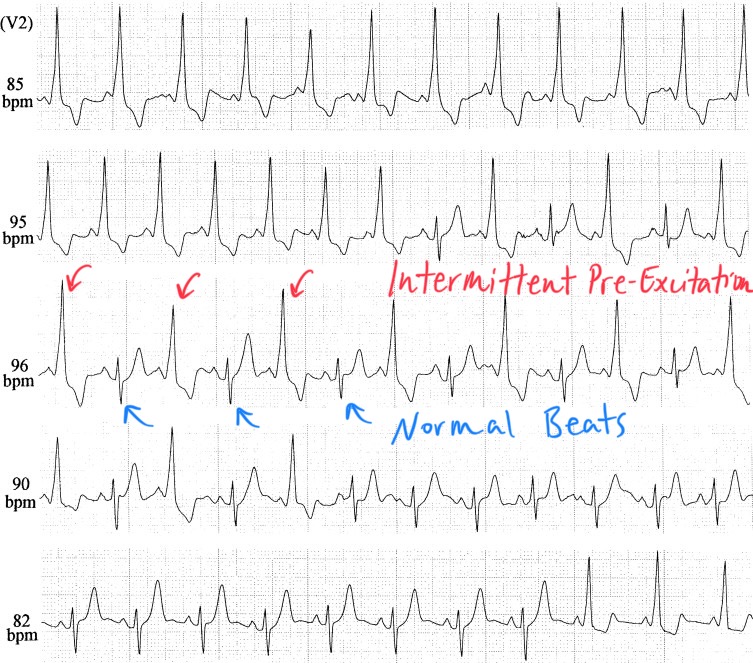

Mechanism 3: Alternating Pre-Excitation in Wolff-Parkinson-White (WPW) Syndrome

Electrical alternans can also occur in the setting of Wolff-Parkinson-White (WPW) syndrome, where it results from beat-to-beat variation in pre-excitation through an accessory pathway.

How It Happens:

-

In WPW, impulses from the atria may conduct to the ventricles via both the AV node and an accessory pathway (e.g., the Bundle of Kent).

In some cases, some beats are conducted with pre-excitation (i.e., via the accessory pathway), while others use the AV node exclusively.

This produces an alternating pattern of QRS morphology:

Pre-excited beats: Wide QRS with delta wave and abnormal axis

Non-pre-excited beats: Narrow QRS via the normal His-Purkinje system

The result is a beat-to-beat alternation in QRS width and shape, a form of electrical alternans caused by conduction variability, not mechanical factors or AV nodal reentry.

ECG Characteristics:

Alternating wide and narrow QRS complexes

May see intermittent delta waves on pre-excited beats